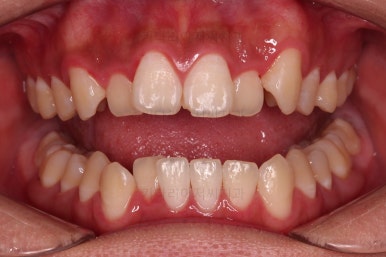

초기 6개월 이내에 어느 정도 치열이 가지런해 졌네요.

중간평가 들어갑니다.

앞니가 많이 뻗쳤나요?

그렇지 않죠.

대신 처음에는 삐뚤어서 가려져 있던 부정교합이 드러나면서 최소한 윗니는 교합을 위해 후방이동이 필요한 상황이긴 했습니다.